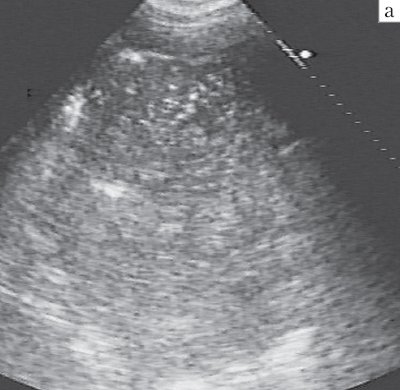

Блокированный абсцесс представлял собой раннюю, закрытую, стадию деструкции легкого с образованием гнойной полости, окруженной легочной паренхимой и не сообщавшейся с бронхиальным деревом. Эхографически он имел вид округлого очага, чаще с однородной эхоструктурой, представленной ан- или гипоэхогенным жидким содержимым с эхогенной взвесью (гнойный детрит), но без гиперэхогенных сигналов от воздуха. Взвесь различалась по эхогенности, плотности и характеру распределения в полости деструкции. Как правило, она была мелкозернистой, достаточно рыхлой и диффузно заполняла весь абсцесс, не вызывая диагностических трудностей (рис. 2).

б) Гипоэхогенным содержимым с плотной взвесью, имитирующей периферический рак.

При равномерно высокой плотности густое гнойное содержимое имитировало эхогенную опухолевую ткань, в связи с чем требовалась дифференциальная диагностика с периферическим раком легкого. Неоднородная взвесь могла формировать локальные скопления повышенной эхогенности, имитирующие секвестры, но при интенсивном вдохе или кашле частицы эхогенного участка смещались независимо друг от друга, быстро изменяя его форму и контуры (рис. 3). Истинные внутриполостные тканевые фрагменты сохраняли постоянную форму, перемещаясь целиком (рис. 4).